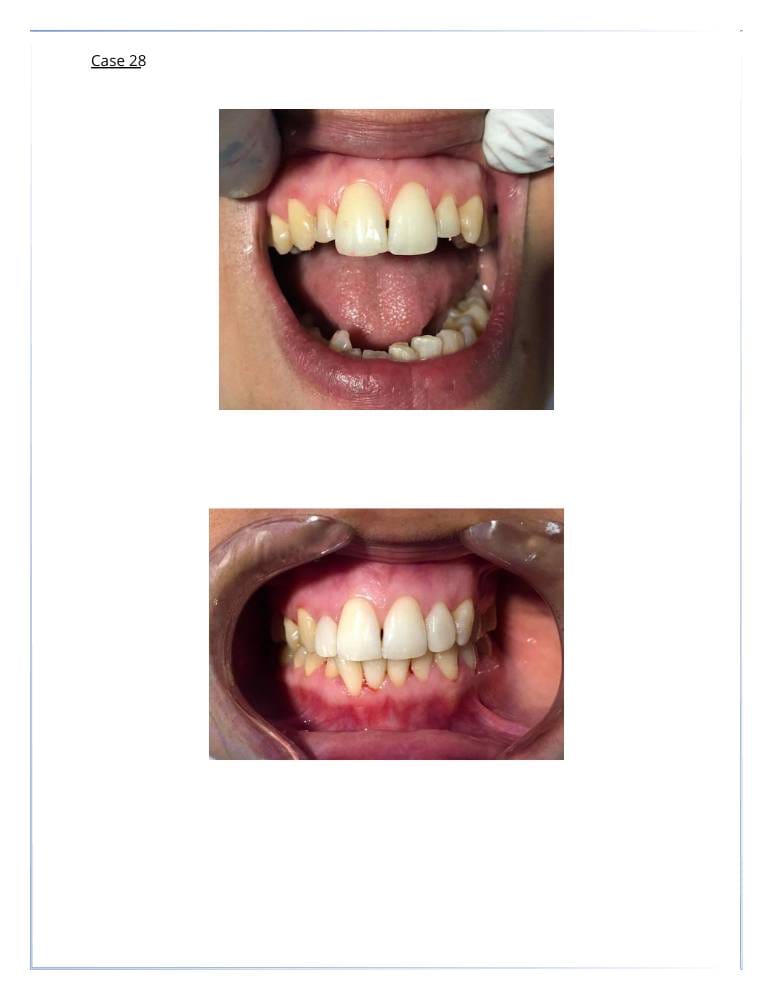

التجميل السني

- اكدت الدراسات ان شكل ولون الاسنان يساهم في تغيير شكل وجمال الوجه بنسبة 47%

تبييض الأسنان. - قشور الفينير (veneer) لتغطية الأسنان المعيبة.

- إعادة تشكيل وتعديل الأسنان لتحسين المظهر.